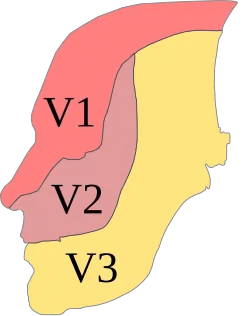

Die Lokalanästhesie (; lateinisch locus „Ort“, altgriechisch ἀν an „ohne“ und αἴσθησις aisthēsis „Wahrnehmung“ mit Alpha privativum, demnach örtliche Empfindungslosigkeit, lokale Schmerzausschaltung) oder örtliche Betäubung ist – im Gegensatz zur Allgemeinanästhesie (umgangssprachlich Vollnarkose) – eine auf einen kleinen Bereich beschränkte Ausschaltung des Schmerzes im Bereich von Nervenendigungen oder Nervenleitungsbahnen, ohne das Bewusstsein des Patienten zu beeinträchtigen.[1] Die häufigste ambulante Anwendung findet die Lokalanästhesie in der Zahnmedizin. Dabei wird vor allem unterschieden zwischen der Infiltrationsanästhesie (auch Terminalanästhesie), der intraligamentären Anästhesie und der Leitungsanästhesie (auch Regionalanästhesie). Die Leitungsanästhesie am Unterkiefer erfolgt insbesondere am Nervus alveolaris inferior als Teil des dritten Astes des Nervus trigeminus, des Nervus mandibularis, während die Leitungsanästhesie am Oberkiefer am Nervus maxillaris erfolgt.[2] Das Ziel ist die Schmerzausschaltung bei allen schmerzhaften Eingriffen im Fachgebiet der Zahn-, Mund- und Kieferheilkunde. Die Lokalanästhesie leistet einen entscheidenden Beitrag zur Vermeidung der Dentophobie (Zahnbehandlungsangst), bei entsprechender schmerzarmer beziehungsweise schmerzloser Injektionstechnik auch zur Vermeidung der Trypanophobie (Spritzenangst).[3] Die Durchführung einer Lokalanästhesie steht unter (Zahn-)arztvorbehalt.

Folgende Leitungsanästhesien können (auch kombiniert) je nach Eingriff notwendig sein, um eine ausreichende Anästhesie zu erreichen.

| Nerv | Anästhesiertes Gebiet |

|---|---|

| Leitungsanästhesie des Nervus alveolaris inferior (V3) | Knochen, Schleimhaut und Zähne einer Unterkieferhälfte |

| Extraorale Leitungsanästhesie des Nervus alveolaris inferior (V3) | dto. |

| Leitungsanästhesie des Nervus lingualis (V3) | Vordere zwei Drittel einer Zungenhälfte |

| Leitungsanästhesie des Nervus buccalis (V3) | Schleimhaut der Wange |

| Leitungsanästhesie des Nervus mentalis (V3) | Schleimhaut, Haut und Muskel im Kinnbereich einer Seite |

| Extraorale Leitungsanästhesie des Nervus mentalis (V3) | dto. |

| Leitungsanästhesie des Nervus palatinus major (V2) | hintere zwei Drittel der Gaumenschleimhaut einer Seite und das Zahnfleisch der Oberkiefer-Seitenzähne |

| Leitungsanästhesie des Nervus nasopalatinus (Nervus incisivus) (V2) | vorderes Drittel der Gaumenschleimhaut einer Seite |

| Leitungsanästhesie des Nervus maxillaris (V2) | eine Oberkieferhälfte |

| Extraorale Leitungsanästhesie des Nervus infraorbitalis (V2) | über die Rami alveolares alle Zähne einer Oberkieferhälfte und die Haut einer vorderen und oberen Gesichtshälfte |

| Leitungsanästhesie des Nervus facialis (VII) | über sensible Fasern Molaren einer Unterkieferhälfte |